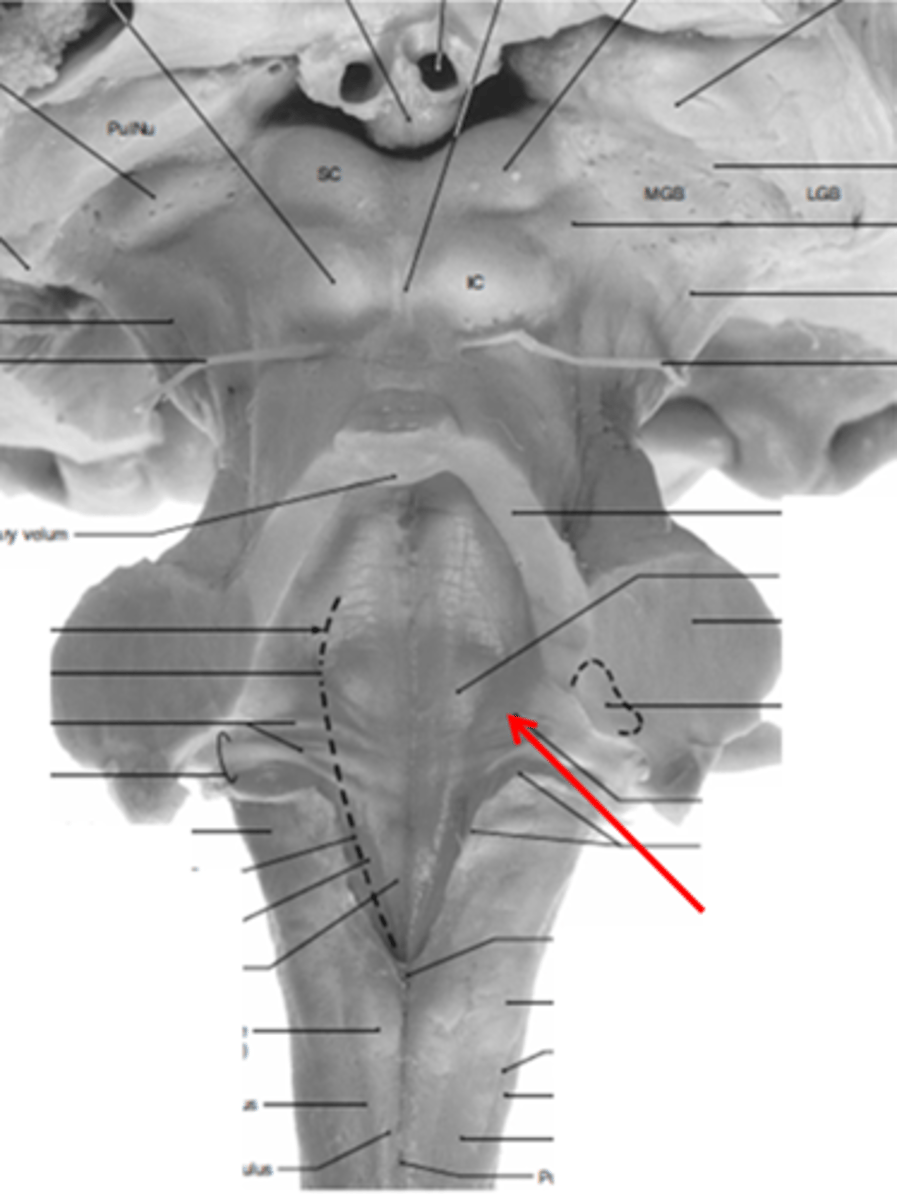

refers to the rostral portion of the medulla since there is no medullary tissue here on the dorsal aspect of the 4th ventricle

open

refers to the caudal portion of the medulla since there is medullary tissue here on the dorsal aspect of the 4th ventricle (therefore it is enveloped by the medulla)

closed

narrowed down portion of the 4th ventricle in the closed portion of the medulla

central canal

two ridges of tissue on the ventral aspect of the medulla, separated from each other by the ventral median fissure

pyramids

area where most corticospinal fibers decussate over the lower medulla, therefore obscuring the ventral median fissure

pyramidal decussation

elongated mounds of tissue lateral to the medullary pyramids

olives

vertical groove dorsolateral to the inferior olive on each side that gives rise to CN IX and X

postolivary sulcus

white matter stalks that connect the medulla to the cerebellum

**these help to form the lateral walls of the caudal portion of the 4th ventricle

inferior cerebellar peduncles

medial paired ridges of tissue on the dorsal aspect of the closed portion of the medulla

tractus gracilis

lateral paired ridges of tissue on the dorsal aspect of the closed portion of the medulla

tractus cuneatus

superior ends of the medial paired ridges of tissue on the dorsal aspect of the closed portion of the medulla, formed by namesake nuclei

gracilis tubercles

superior ends of the lateral paired ridges of tissue on the dorsal aspect of the closed portion of the medulla, formed by namesake nuclei

cuneatus tubercles

V-shaped boundary of the caudal aspect of the 4th ventricle that marks the boundary between the open and closed portions of the medulla

obex

What anatomical aspect of the 4th ventricle is considered its floor?

ventral

refers to the floor of the 4th ventricle

rhomboid fossa

What forms the floor (rhomboid fossa) of the 4th ventricle?

dorsal surfaces of pons tegmentum and open medulla

inferior angle of the floor of the 4th ventricle

obex

vertical groove running in the floor of the 4th ventricle that separates it into right and left halves

dorsal median sulcus

vertical groove lateral to the dorsal median sulcus of the 4th ventricle

**same one that separated the alar and dorsal plates in the neural tube during development

sulcus limitans

refers to most of the floor of the 4th ventricle lateral to the sulcus limitans

**namesake nuclei are here

vestibular area

triangular region located in the caudal portion of the rhomboid fossa of the 4th ventricle, where the dorsal motor nucleus of CN X is

vagal trigone

Which parasympathetic nucleus is found in the vagal trigone of the 4th ventricle?

dorsal motor nucleus of X

triangular region located most medially in the caudal portion of the rhomboid fossa of the 4th ventricle, where the CN XII nucleus is

hypoglossal trigone

part of the 4th ventricle superior to the vagal and hypoglossal trigones (still medial to the sulcus limitans)

medial eminence

small bump located in the caudal portion of the medial eminence which forms from the motor fibers of CN VII as they wind around the underlying CN VI nucleus

facial colliculus

pigmented area that looks blue near the superior aspect of the sulcus limitans; cluster of noradrenergic cells

locus ceruleus

fibers that run horizontally in the central region of the rhomboid fossa of the 4th ventricle

stria medullares

area that helps to make the walls of the obex and is thought to be the "vomit trigger"

area postrema